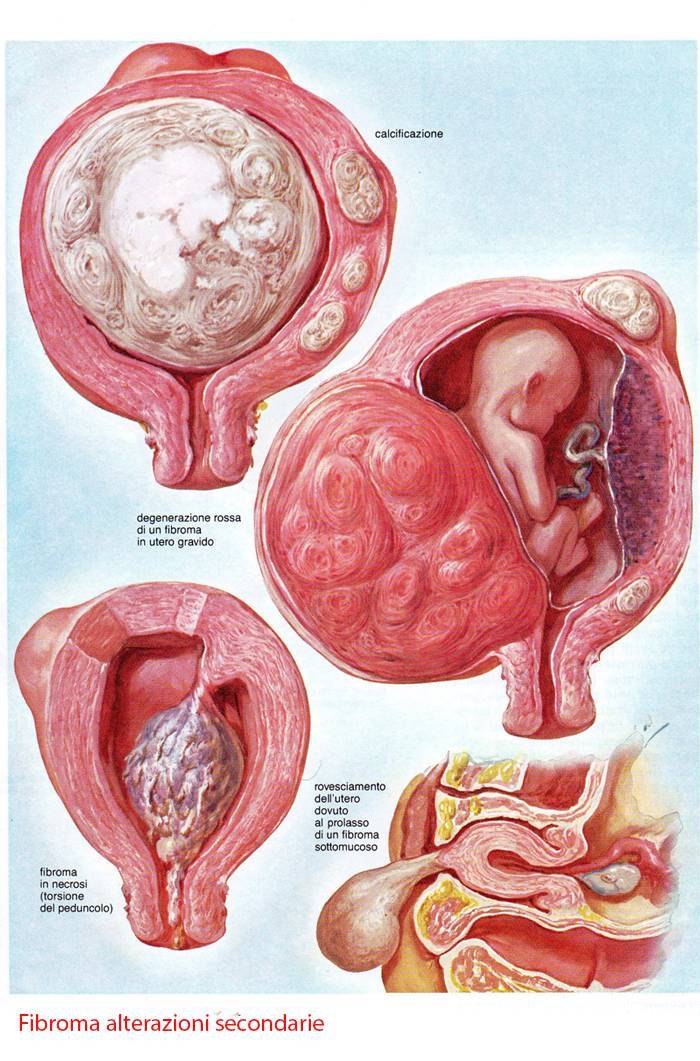

Анатомия женского организма: строение и функции матки